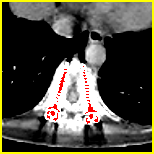

Effect of metal mask projection (SE0-Net vs SE-Net). From Table 1, we can observe the use of instead of improves the performance for at least 4.1 dB in PNSR and reduces MSE from 0.95219 to 0.00074 for all metal sizes. The groups with large metal implants benefit more than groups with small metal implants. As shown in Fig. 4, the artifacts in metal trace of SE0-Net are over-removed or under-removed, which introduces bright and dark bands in the reconstructed CT image. With the help of , SE-Net can suppress the artifacts even when the metallic implants are large and the surrogate data are more consistent with the correct data outside the metal trace.

Effect of sinogram padding (SE-Net vs SEp-Net). Sinogram padding mainly improves the performance in the group with the largest metal objects, with a PSNR gain of 0.15 dB and an MSE reduction of 0.00048. As shown in Fig. 4, the model with sinogram padding restores finer details of soft tissue between large metallic objects because more correct information is retained by periodic padding than zero-padding.

Effect of learning with (SEp-IE-Net vs Ours). When is jointly restored with the corrupted , the sinogram correction performance is affected with an increment of 0.00033 in MSE and of 0.7 dB in PSNR. More details of soft tissue around metal are retained and the image becomes sharper, as shown in Fig. 4.